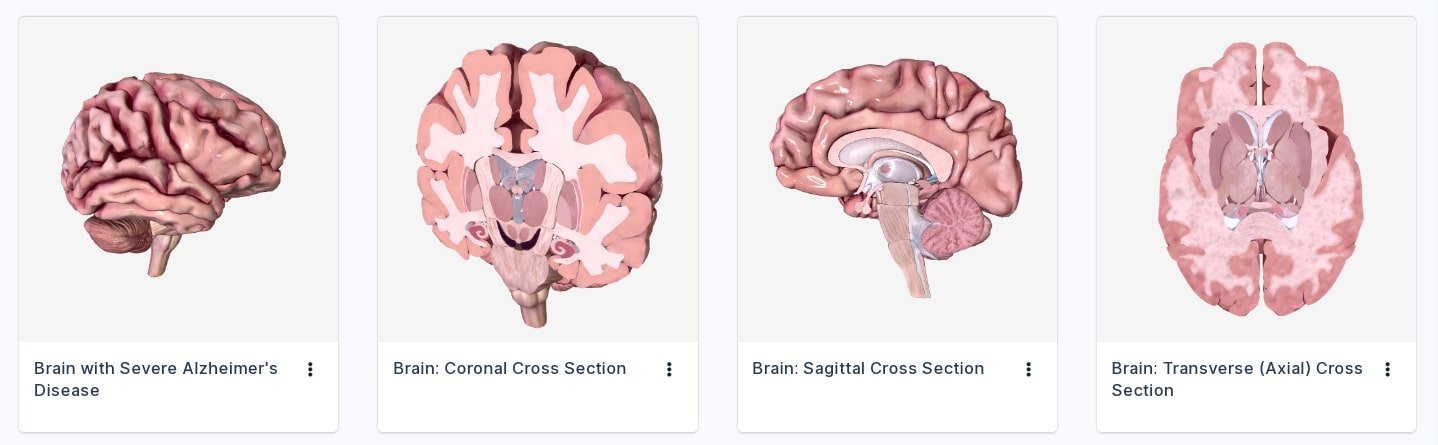

અલબત્ત, વાત ગૂગલ જેવી ટેક કપનીની હોય એટલે દેખીતું છે કે વાત માત્ર બે-ઘડીની રમતથી અટકે નહીં.ગૂગલે હવે આ રમત ઘણી વિસ્તારી છે. આ માટે બાયોડિજિટલ. () નામની એક કપનીની મદદ લેવામાં આવી છે. આ કપનીએ મેડિકલ પ્રોફેશનલ્સ અને સ્ટુડન્ટ્સ માટે એક સોશિયલ મીડિયા પ્લેટફોર્મ જેવી વ્યવસ્થા વિક્સાવી છે. તેણે એક ઇન્ટરઅક્ટિવ ૩ડી સોફ્ટવેર પ્લેટફોર્મ વિક્સાવ્યું છે, જેની મદદથી હ્યુમન એનેટોમી એટલે કે માનવશરીરની સંપૂર્ણ રચના, તેનાં વિવધ અવયવતંત્રો વગેરે જાેઈ-સમજી શકાય છે, તેમ જ રોગનાં કારણ, તેની શરીર પર અસર અને સારવાર વગેરેને વિઝ્યુઅલાઇઝ કરી શકાય છે. દેખીતું છે કે આપણને `વિઝ્યુઅલાઇઝ’ વાળી વાતમાં રસ પડે!

અલબત્ત, વાત ગૂગલ જેવી ટેક કપનીની હોય એટલે દેખીતું છે કે વાત માત્ર બે-ઘડીની રમતથી અટકે નહીં.ગૂગલે હવે આ રમત ઘણી વિસ્તારી છે. આ માટે બાયોડિજિટલ. () નામની એક કપનીની મદદ લેવામાં આવી છે. આ કપનીએ મેડિકલ પ્રોફેશનલ્સ અને સ્ટુડન્ટ્સ માટે એક સોશિયલ મીડિયા પ્લેટફોર્મ જેવી વ્યવસ્થા વિક્સાવી છે. તેણે એક ઇન્ટરઅક્ટિવ ૩ડી સોફ્ટવેર પ્લેટફોર્મ વિક્સાવ્યું છે, જેની મદદથી હ્યુમન એનેટોમી એટલે કે માનવશરીરની સંપૂર્ણ રચના, તેનાં વિવધ અવયવતંત્રો વગેરે જાેઈ-સમજી શકાય છે, તેમ જ રોગનાં કારણ, તેની શરીર પર અસર અને સારવાર વગેરેને વિઝ્યુઅલાઇઝ કરી શકાય છે. દેખીતું છે કે આપણને `વિઝ્યુઅલાઇઝ’ વાળી વાતમાં રસ પડે!

સાઇટ પર ઉપલબ્ધ છે અસંખ્ય મોડેલ્સ

આ સાઇટ પર ફ્રી એકાઉન્ટ બનાવ્યા પછી તમે વધુ એનિમેશન્સ કે મોડેલ્સ જોઈ શકશો. અલબત્ત, આ સાઇટ મુખ્યત્વે મેડિકલ પ્રોફેશનલ્સ માટે છે એટલે ઘણું કન્ટેન્ટ પેઇડ મેમ્બરશીપ પછી જોઈ શકાય છે. પ્રોફેશનલ્સ, આ મોડેલ્સનો ઉપયોગ કરીને પોતાની રીતે ટ્યુટોરિયલ્સ બનાવી શકે છે. https://www.biodigital.com/

આ સાઇટ પર ફ્રી એકાઉન્ટ બનાવ્યા પછી તમે વધુ એનિમેશન્સ કે મોડેલ્સ જોઈ શકશો. અલબત્ત, આ સાઇટ મુખ્યત્વે મેડિકલ પ્રોફેશનલ્સ માટે છે એટલે ઘણું કન્ટેન્ટ પેઇડ મેમ્બરશીપ પછી જોઈ શકાય છે. પ્રોફેશનલ્સ, આ મોડેલ્સનો ઉપયોગ કરીને પોતાની રીતે ટ્યુટોરિયલ્સ બનાવી શકે છે. https://www.biodigital.com/